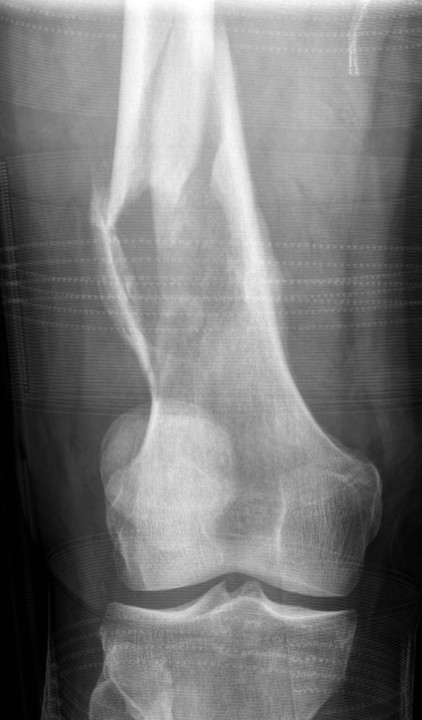

Osteosarcoma of the distal femur

Osteosarcomas of the proximal tibia

Xray

Typically metaphysis of long bones

- distal femur 35%

- proximal tibia 20%

Features

- new bone formation / osteoid

- permeative cortical destruction

- wide zone of transition

- periosteal reaction

- soft tissue mass